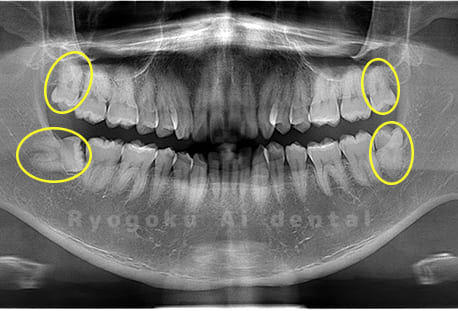

Case03

- 原因

- 上顎、下顎の親知らず

- 治療内容

- 上下4本の親知らずを抜歯したケースです。

<リスク・副作用>

手術後は痛み、腫れ、痺れなどの副作用が生じる場合があります。